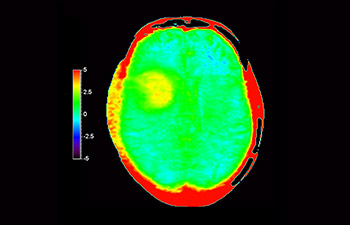

Cerveau avec glioblastome

avec 3D APT